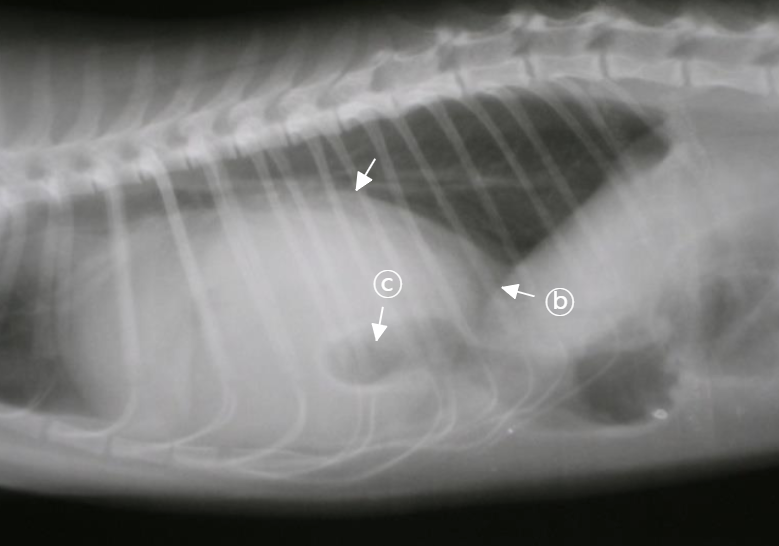

PPDH

: 복강 안 장기가 심낭 안으로 들어가 ⓐ 심장이 매우 커 보임.

- 선천성 질병이라 어릴 때 발생. (PE는 어릴 때 잘 X)

- ⓑ PPDH는 diaphragm silluette이 명확하지 않음.

- ⓒ 장에 차 있는 공기 음영이 보임